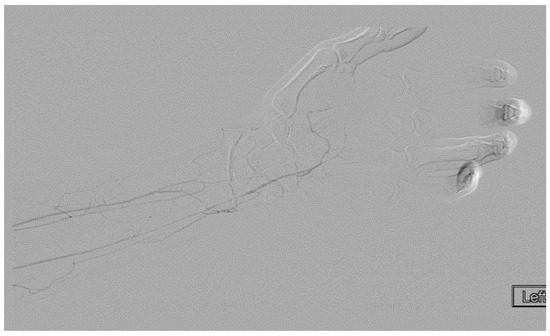

A heparin drip was then initiated, and she was taken to the catheterization lab for thrombolysis. This was carried out with Alteplase for 48 h as the patient had strong collaterals and was not in limb-threat (Figure 7, Figure 8, Figure 9, Figure 10 and Figure 11). However, her radial artery remained occluded. She was then taken to the operating room for thromboembolectomy of the left brachial and radial arteries (Figure 12). She was continued on anticoagulation post-operatively and was discharged.

Figure 10.

Angiography of the radial and ulnar arteries as well as the palmar arch and digital branches in an ATOS patient with a brachial thrombus.